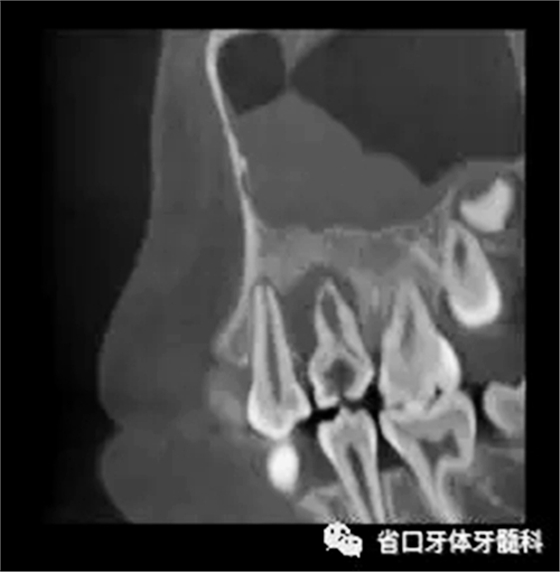

圖3 CBCT(2016-11-13):15由髓腔至根管內(nèi)見(jiàn)團(tuán)塊阻射影像,阻射影中央為透射影,根尖1/3處見(jiàn)根管膨大,腭側(cè)牙槽骨破壞,根尖周低密度影范圍大,上頜竇黏膜增厚。